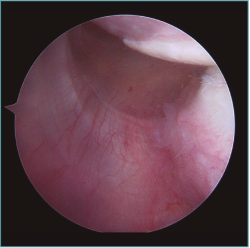

Figura 4. Visión desde portal posterior del hombro izquierdo. Paciente con inestabilidad de hombro hiperlaxo. Se identifica un gran receso capsular posteroinferior.

Figura 5. Mismo paciente que la Figura 4. Se visualiza la gran plicatura capsulolabral posteroinferior con un ancla de doble sutura.